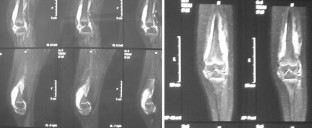

Inflammatory or septic arthritis due to Mp is an extremely unusual manifestation in children, and the functional outcome of the joints is difficult to be predicted. Two cases with Mp infection are presented. The first patient had positive PCR for Mp after hip aspiration and arthrotomy with thorough irrigation and debridement. A flattened femoral head was detected during the follow-up, which became quite spherical a year after. An arthrotomy with medial synovectomy of the knee was performed in the second patient. Lack of full knee extension was presented during the first 3 months, which gradually decreased to 7° in the final follow-up. The suspicion of Mp infection with extra-pulmonary involvement in children is mainly based on clinical, epidemiological and radiological data, but laboratory testing is required for confirmation. Rapid diagnosis of probability consists of serum tests, and their results are essential for early therapeutic planning. The direct diagnosis of Mp DNA through polymerase chain reaction (PCR) provides specificity and sensitivity. Very few cases of arthritis associated with Mp infection have been published but not with the severity of our cases. Clinical suspicion of Mp infection is of great importance, and the outcome depends on early diagnosis and specific treatment.

Fig. 1

Fig. 2

Fig. 3

Fig. 4

Fig. 5

Fig. 6

Fig. 7

Fig. 8

Fig. 9